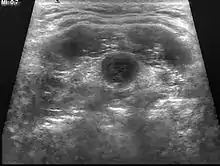

Ultrasound | Image capture of the degree of mass and its surrounding tissues. |